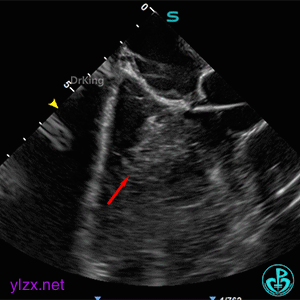

ICE下多切面观察封堵器形态及瓣膜活动状况

封堵器骑跨于室间隔两侧,周围瓣膜正常摆动。